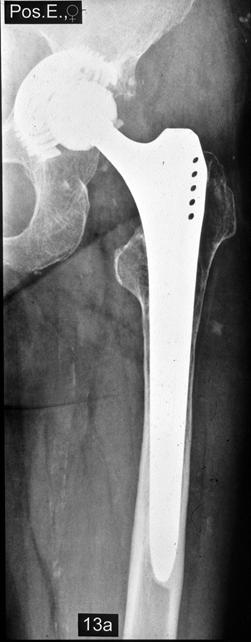

Fallbeispiel

Weiblich, 78 Jahre. Die

Bilder zeigen eine deutlich gelockerte zementierte

Hüftprothese. Der Knochen um den Zement ist stellenweiße

papierdünn

Zustand nach Austausch der

zementierten Prothese durch eine Bicon-Pfanne sowie

einen SLR-Schaft.

Die Röntgenbilder zeigen das Ergebniss nach 13 Jahren.

Die nun 91 jährige Patientin ist gut gehfähig und völlig

beschwerdefrei.